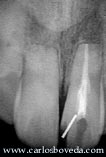

Esta secuencia de imágenes clínicas nos permite detalla tanto el abordaje como el contenido del espacio pulpar. Se remueve e inmediatamente queda visible el extremo apical del conducto, en este caso relleno con amalgama de su cirugía previa.

Vista detallada de la preparación ejecutada. En este momento el problema viene dado por la presencia de la amalgama apical y por la facilidad de un eventual desalojo de la misma en el caso que se generen fuerzas verticales sobre su eje. Además, la longitud radicular nos hace pensar en lo inadecuado que pudiera ser utilizar gutapercha si se pretende obtener un sellado endodóntico confiable. Estas y otras consideraciones nos hacen decidir colocar MTA a través del conducto como material de obturación.

Una vez colocado el MTA se sella con un bloque de vidrio ionomérico tipo I.

Por último, el abordaje coronal se protege provisionalmente con un cemento no eugenólico. Inmediatamente se toman las vistas radiográficas una vez ejecutado el retratamiento endodóntico en 1 sesión.

El caso se mantiene asintomático, por lo que se refiere para nueva restauración y se hace el primer control a los 6 meses.(restauradora por el Dr. Tomás J. Seif R. - tseif@cantv.net). Aquí se pueden comparar las imágenes iniciales y las del primer control.